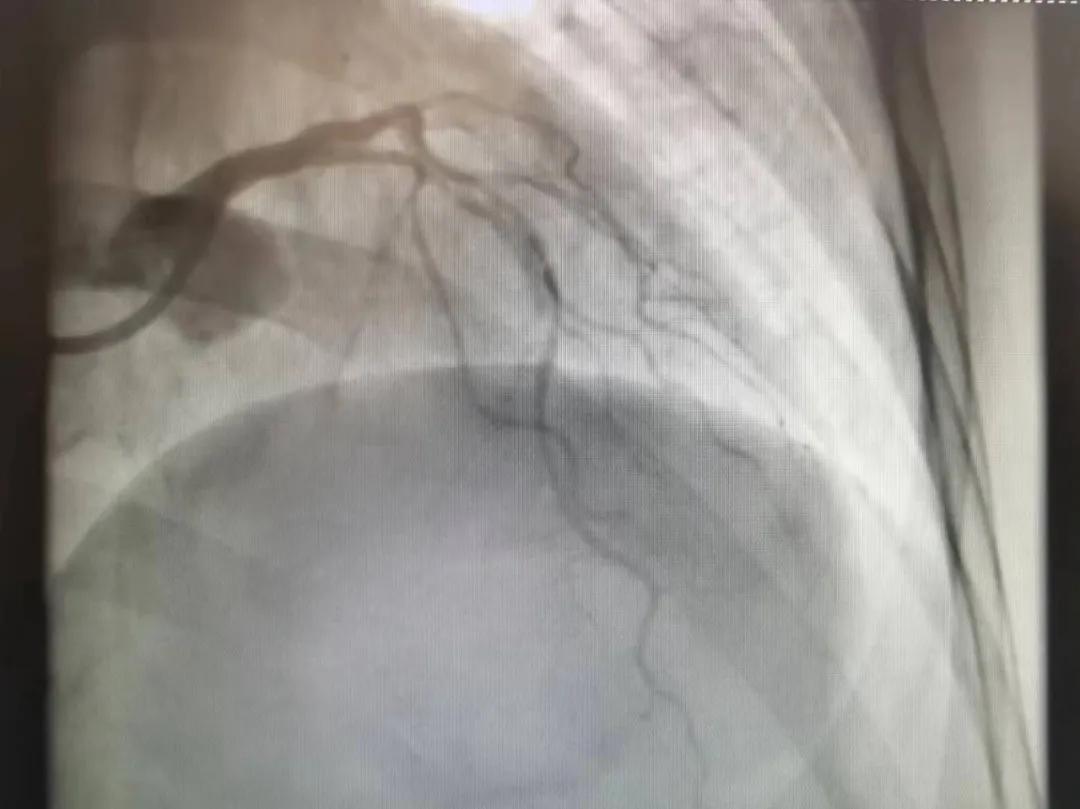

王瑾院長(zhǎng)和李慧新主任帶領(lǐng)介入團(tuán)隊(duì)充分評(píng)估,決定行前降支冠狀動(dòng)脈鈣化病變旋磨術(shù),術(shù)中應(yīng)用1.5mm旋磨頭,以15萬(wàn)-17萬(wàn)轉(zhuǎn)/分速度共對(duì)病變旋磨3次,累計(jì)旋磨時(shí)間60秒,后復(fù)查造影示鈣化明顯減輕,為后續(xù)操作創(chuàng)造了良好條件,隨后應(yīng)用預(yù)擴(kuò)張球囊、切割球囊再次處理病變,并順利植入支架1枚,復(fù)查造影顯示支架膨脹及貼壁良好,無(wú)夾層、血腫、慢血流等情況,手術(shù)順利完成。患者術(shù)后無(wú)不適,胸悶、胸痛癥狀明顯緩解,順利出院。

術(shù)后